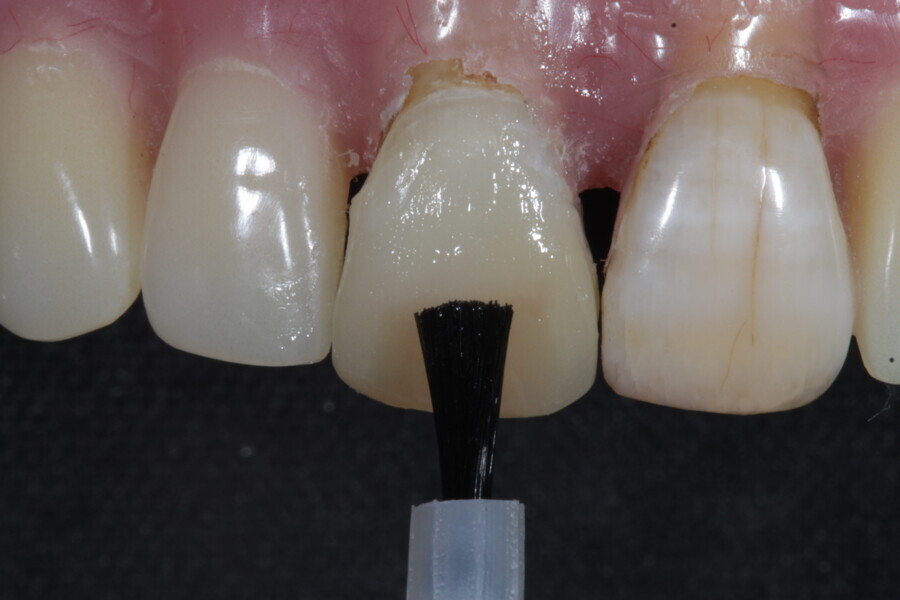

1. functional and aesthetic reconstruction of a maxillary anterior tooth using fibre-reinforced flexible micro-posts after endodontic treatment (Figs. 3–20);

Example 1—showing functional and aesthetic reconstruction of a maxillary anterior tooth using fibre-reinforced flexible micro-posts after endodontic treatment.